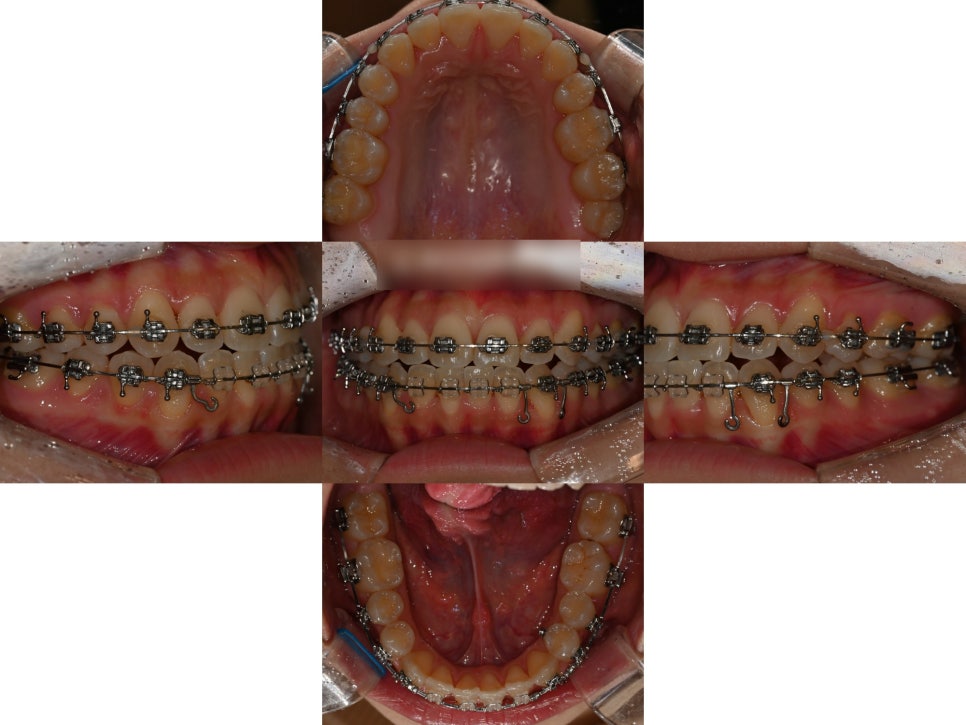

점점 긴밀해져가는

교합의 변화를 확인할 수 있습니다.

중간마다 안모의 조화를 체크하는 것도

잊지 않고 꼼꼼하게 확인합니다.

환자분이 잘 협조해주신 덕분에

치료가 생각보다 빠르게 종결 되었습니다.